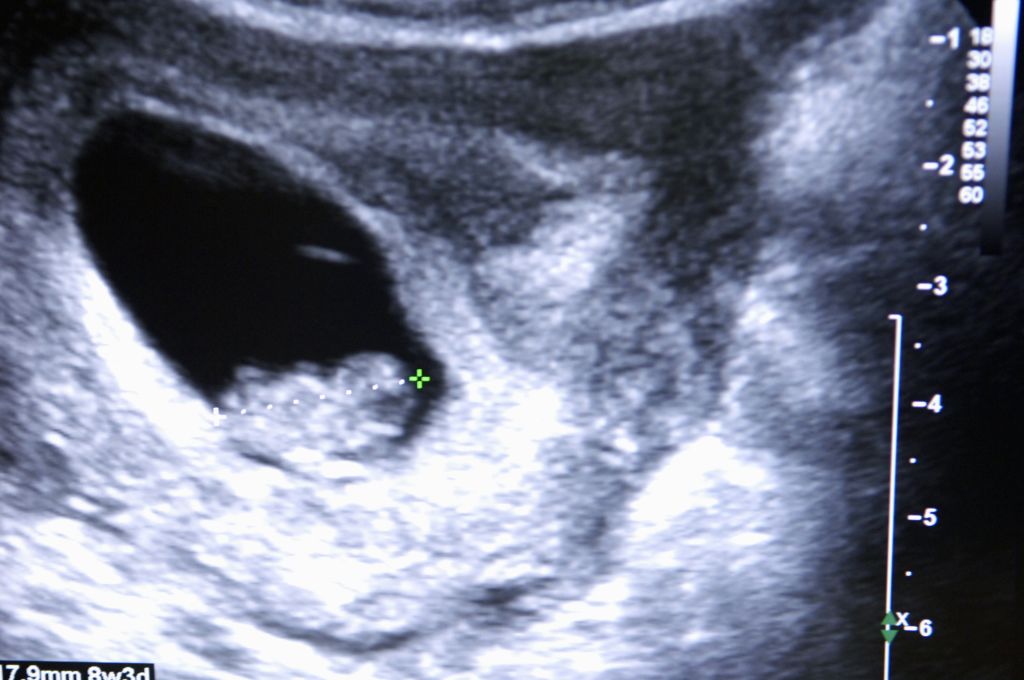

A terhesség első heteiben az ultrahangfotók még alig mutatnak többet egy apró, pulzáló pontnál, amely a fejlődő embriót jelzi. Az első trimeszter végére azonban már jól kivehetővé válik a fej és a végtagok kezdeménye, sőt, egyes esetekben a baba mozgása is megfigyelhető. Ezek a korai képek gyakran homályosak, mégis hatalmas érzelmi jelentőséggel bírnak a leendő szülők számára.